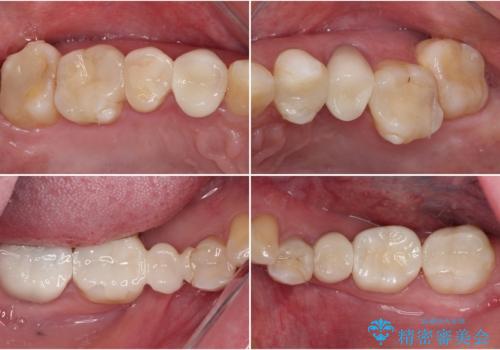

- クラウンから金属の土台が見えてきてしまったとのことで、作り替えを希望して来院された患者様です。

前歯や金属が露出している歯、痛みを感じる歯を中心に、オールセラミッククラウンにて補綴治療することとしました。

以前はセラミッククラウンのフレームとして金属が使用されており、歯肉の経年変化やセラミックのすり減りなどにより、金属が見えるようになってくることがあります。

現在は金属の代わりに強化セラミックを使用したオールセラミッククラウンが主流です。金属色が気になる方はご相談ください。